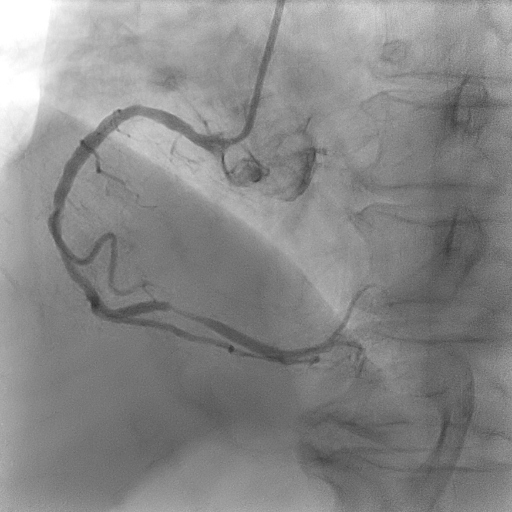

Coronary angiogram showed two vessel disease with severe stenosis at the obtuse marginal (OM), distal left circumflex (LCx) artery and distal right coronary artery (RCA) with mild disease at the proximal left anterior descending artery (LAD).